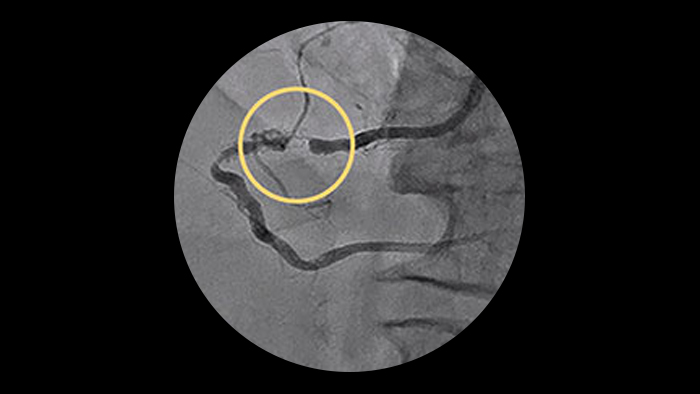

Ostial and bifurcation lesions

Ostial and bifurcation lesions represent nearly 40% of complex PCI’s3